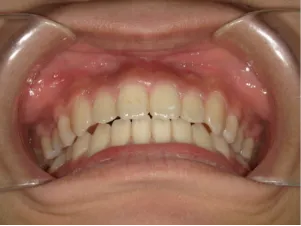

治療後⑤中3:咬合治療終了 マルチブラケット法の期間は9か月

*出っ歯、過蓋咬合、口唇閉鎖不全の改善

*咬合治療用モノブロック装置(筋機能的咬合誘導装置)へ移行

*口唇閉鎖不全がなおり奇麗な口元に改善

*就寝時に使用するモノブロック装置(筋機能的咬合誘導装置)